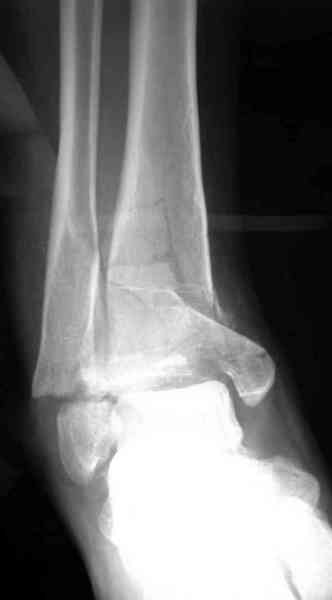

Дополнительные ренгенограммы после дистракции и

обязательная комьютерная томография дают возможности разузнать топографию расположения фрагментов, что немаловажно для планирования хирургического доступа.

По апексу фрагмента ориентируется при планировании

фиксации, также предоперационно определяется

направление фиксирующего материала: шурупа или спицы с упорной площадкой.

Первичная пластина или интрамедуллярный фиксатор на малоберцовую зависит от характера перелома, косые и многооскольчатые пластинами, а поперечных можно интрамедуллярными фиксаторами. Восстановленная длина малоберцовой служит ориентиром и помогает определению высоты большеберцовой во время восстановления.

Переломы пилона сопровождаются ударом со сминанием в метафизарной части большеберцовой, то есть со значительной потерей костного объема.

При репозиции суставных поверхностей образуются полости в метафизарных отделах, без заполнения их

структуральными элементами невозможно предохраниться от посттравматической деформации. Латеральная колонна удерживается малоберцовой поэтому голень деформируется в варус.

Здесь выставлена пара случаев перелома пилона, оба

случая леченные этапным наружным фиксатором.